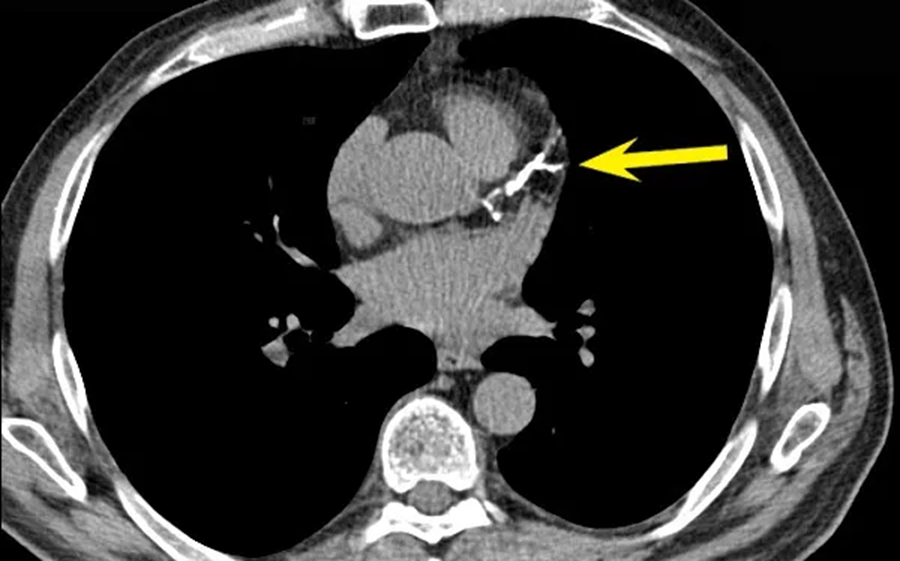

КТ сердца позволяет не только зафиксировать факт наличия атеросклеротических изменений, но и оценить тип бляшек, что критично для прогноза. С помощью плотностной шкалы Хаунсфилда томограф определяет структуру отложений: мягкие бляшки имеют низкую плотность (менее 60 HU), состоят преимущественно из липидов и обладают высокой склонностью к разрыву. Такие образования считаются наиболее опасными, поскольку они нередко становятся причиной внезапных инфарктов даже при умеренном стенозе.

Смешанные бляшки включают в себя и жировые, и кальцинированные компоненты. Они менее склонны к разрыву, но всё ещё представляют риск. Плотные кальцинированные бляшки (свыше 130 HU) чаще стабильны, однако могут значительно ограничивать кровоток, если занимают большую часть просвета сосуда. Именно способность КТ к количественной оценке плотности и распределения этих компонентов делает метод особенно ценным при оценке риска коронарных событий. Дополнительно программа может визуализировать оболочку бляшки – тонкая капсула указывает на нестабильность, в то время как толстая оболочка – на относительную безопасность.